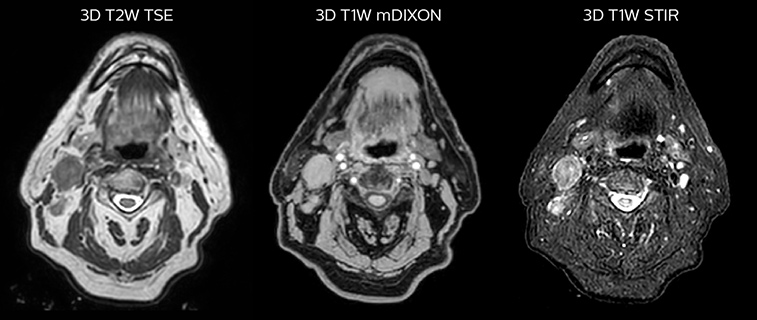

LaTour 3D Stir mDIXON MRI scans

T2W 3D, 3D STIR and mDIXON MRI scans.